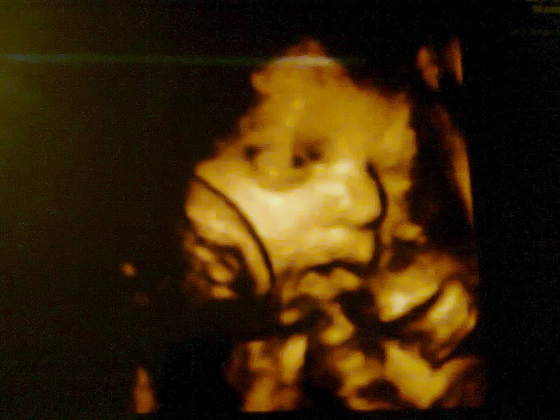

...LEKARZE, BADANIA, I ZNOWU LEKARZE ITD. kurcze już 2 lata. Pierdzielę 6-ki nie widac nie mogę teraz wydac 300 zł bo lekarz zgarnie 150 i zapewne jeszcze USG doliczy

a tu

czekamy